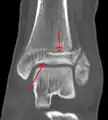

A triplane fracture of the ankle as seen on CT

- Triplane fractures are a special type of fracture that involves the immature skeleton. It has a coronal plane in the metaphysis, an axial plane in the physis, and a sagittal plane in the epiphysis.[14]